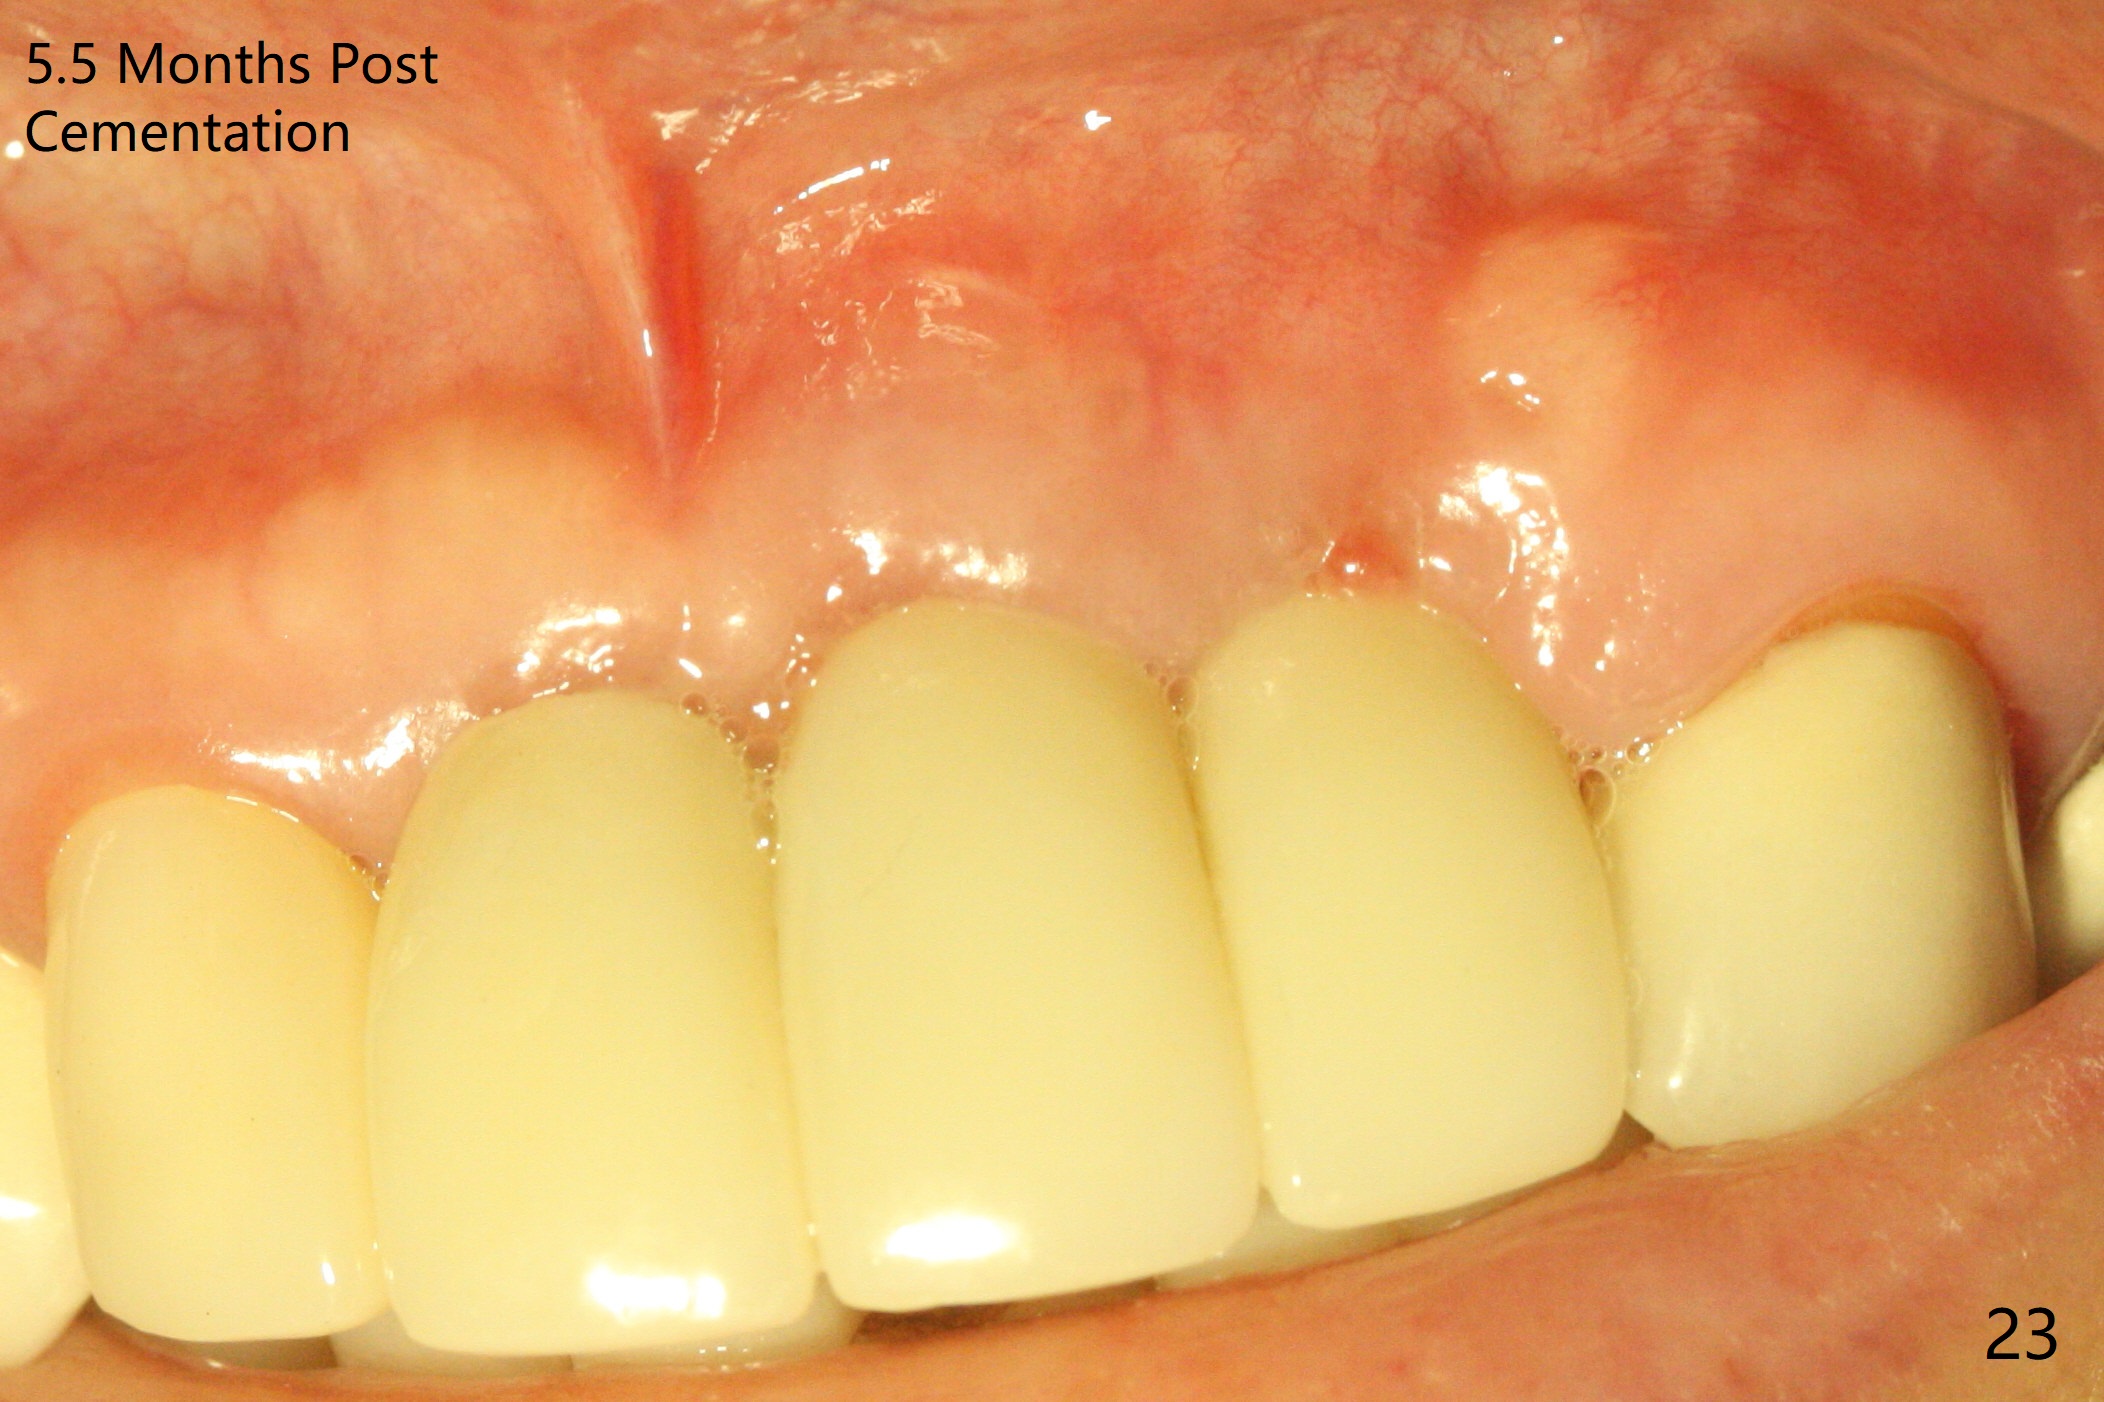

Incision shows exposure of microthreads at #9 and major threads at #10 due to buccal placement (Fig.1). There is bone palatal to the implant at #10 (Fig.2 P), to which a new implant will move. After implant removal, a narrower 1-piece implant (2.5x14(4) mm) is placed palatally at #10 (Fig.3,4) in combination of guide and free hand. At the site of #9 after implant removal, the guide is not used; a 3x17 mm angled 1-piece implant is placed with bad trajectory (Fig.5,6). After re-adjustment (Fig.7), the implant is placed at the right orientation (Fig.8). It appears that the guide is helpful. Allograft is placed mainly buccally (Fig.9,10 *), followed by a piece of collagen membrane (Fig.11). After tension release, flaps are approximated (Fig.12). The buccal gingiva at #9 and 10 recede nearly 2 months postop (Fig.13). Less recession at #9 is associated with more inflammation (Fig.14). The margin of the provisional is adjusted for gingival margin down growth and easy self cleaning with Water Pik (Fig.15). One month later, the gingival inflammation reduces, while there is no obvious buccal collapse (Fig.16,17). Impression is taken after laser gingivectomy nearly 4 months postop (Fig.18). While the gingiva around the implant at #9 is inflamed (periimplantitis?), the gingival cuff at #10 is well formed 5.5 months postop immediately before cementation (Fig.19). The buccal concavity at #10 is minimal (Fig.20). The gingival inflammation at #9 will be hopefully resolved after cementation of the final restorations (Fig.21). There appears to be new bone formation around the coronal implant threads 5.5 months postop (immediately post cementation, Fig.22). The microthreads at #9 may be not covered by the bone, the reason for the gingival erythema. The redness at #10 is asymptomatic 5.5 months post cementation (Fig.23). 粘固后两年牙槽嵴骨质并没有再生(图二十四),说明第一术中植体必须植入骨下(基台部分要长,否则难于修复),第二牙槽嵴处不应该有压力,植入2.5毫米植体,最后钻头应该是2.5毫米,骨下1-3毫米(尝试项目)。